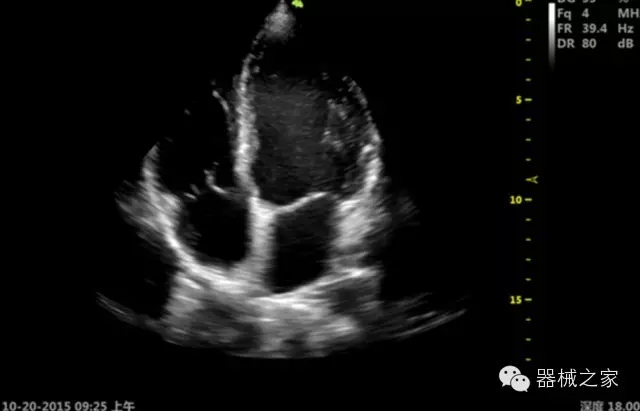

臨床圖片賞析

產(chǎn)品特點(diǎn)

優(yōu)異的成像技術(shù)

·亞陣元技術(shù):獨(dú)有的亞陣元技術(shù),對獨(dú)立晶片做二次切割,減少旁瓣偽像,增加臨床診斷的準(zhǔn)確性;

·μ-Scan微米成像技術(shù):開立獨(dú)有的μ-Scan技術(shù),還原出真實(shí)細(xì)膩、層次對比優(yōu)異的二維圖像;

·倒相諧波成像技術(shù):倒相諧波技術(shù)在去除基波信號的基礎(chǔ)上獲取兩倍二次諧波信號,提高組織圖像的對比分辨力;

·智能微血流成像技術(shù):智能微血流捕捉技術(shù)可以提取出隱藏在背景噪聲中的弱血流信號,大大提高低速血流的敏感性;

·心功能綜合指數(shù)(TEI指數(shù)):用于左、右心室整體心臟收縮舒張功能評估的測量方法;

·全方位可調(diào)M型:有利于更好的觀察心腔大小及室壁階段性運(yùn)動的異常情況;

·組織多普勒成像(TDI):TDI可定量評價心肌運(yùn)動,判斷是否有局部病變,還可評價早期的舒張功能;